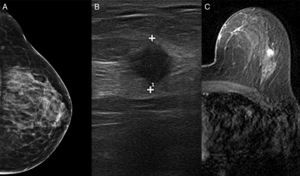

La exploración física fue normal. Las pruebas de imagen complementarias (fig. 2) incluyeron mamografía, ecografía y resonancia magnética. La mamografía mostró tejido fibroglandular, pero no detectó una masa focal. La ecografía identificó un nódulo homogéneo hipoecoico de 10mm en la mama izquierda. La resonancia magnética localizó la lesión en el cuadrante superoexterno de la mama izquierda, con características cinéticas de malignidad. No se encontraron otras lesiones. Se realizó una biopsia con aguja gruesa. El resultado histológico reveló un carcinoma ductal, RE+++, RP+++, cadherina-E+++, Ki-6710% y HER-2+.